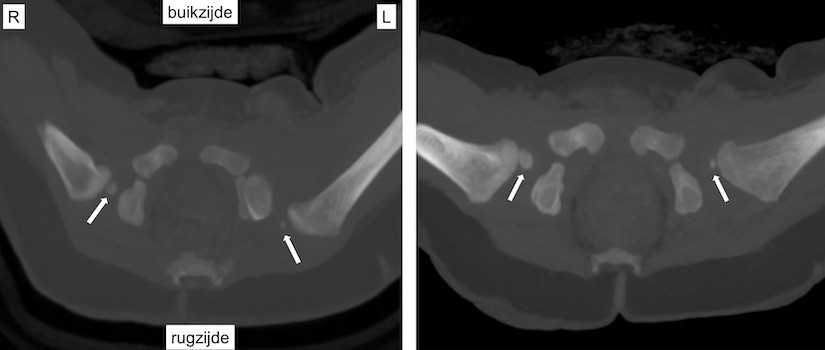

Links: CT-scan van het bekken van een baby van 8 maanden. Dwarsdoorsnede door het heupgewricht. De heupkoppen zijn gemarkeerd met witte pijlen. De linkerheupkop is naar achter (rugzijde) geluxeerd. Dit is op een röntgenfoto niet goed te zien.

Rechts: CT-scan van het bekken van dezelfde baby als figuur 7, 1 maand na repositie. De linkerheupkop staat goed in de kom..

Bij kinderen met heupluxatie kan een CT-scan worden gebruikt om te controleren of de heupkop goed in de heupkom staat als het niet lukt om dit op een andere manier te bekijken.

Omdat een CT-scan een dwarsdoorsnede van het lichaam weergeeft, wordt voor het in beeld brengen van de heup een scan van het bekken gemaakt. Tijdens het maken van de scan lig je op je rug op een tafel die door de scanner schuift.